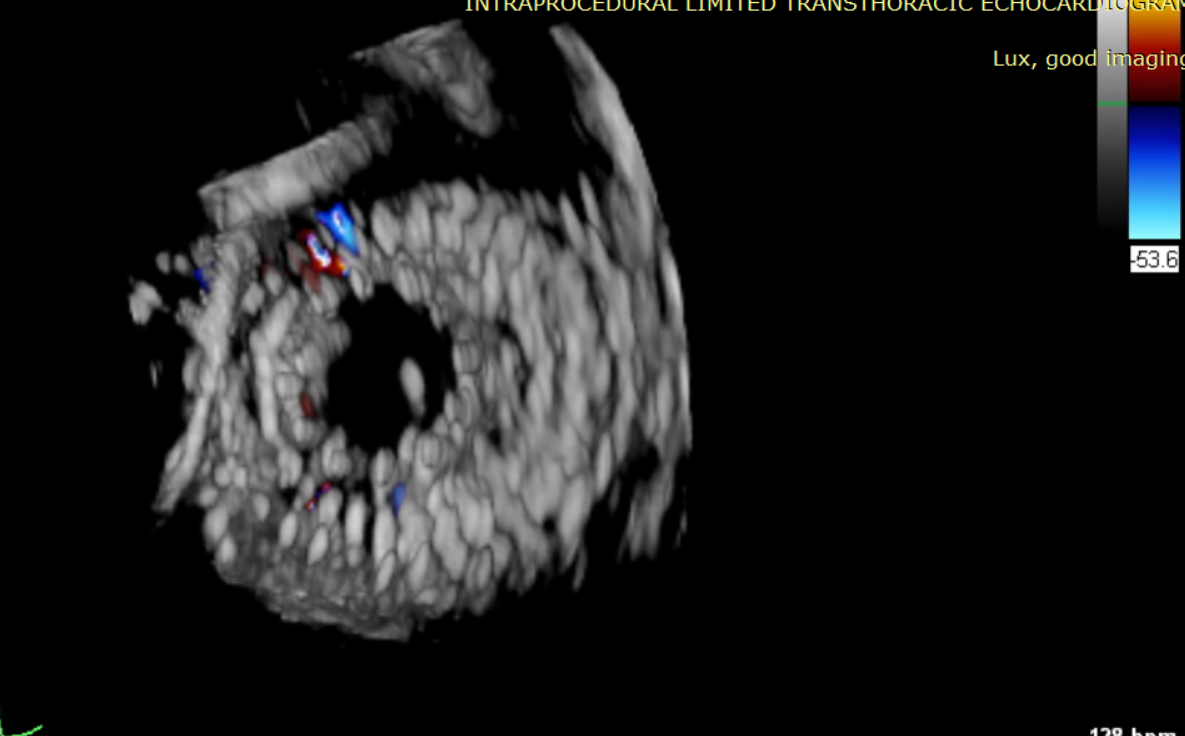

示意圖

LuX-Valve Plus采用經頸靜脈入路,不僅對患者損傷進一步減小,同時為術者提供了便捷的術中操作方式。與一代產品LuX-Valve共同已經為全球數(shù)百名患者提供了有效的治療,最長隨訪時間逾四年,長期安全性和有效性得到充分驗證。